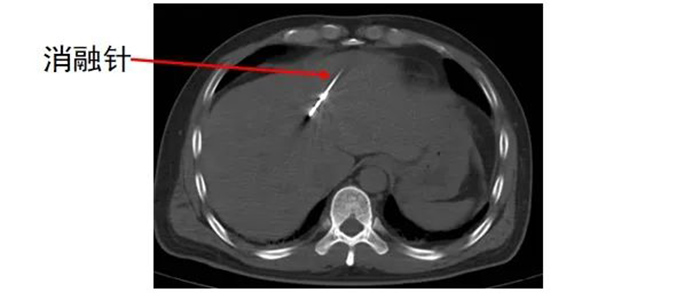

经皮肝恶性肿瘤微波消融术是治疗肝脏恶性肿瘤的局部微创治疗方法,具有创伤小、恢复快、对肝功能影响相对较小等优点。

但如何确保在手术中精准定位,将消融针准确置入肿瘤部位,并根据肿瘤的具体情况,合理控制消融范围和能量,避免损伤周围正常组织,需要医生拥有丰富经验和精准操作技巧,以及较强的判断力、把控力。

齐先生病灶临近大血管、重要脏器。厦门三院专家团队在CT引导下精准定位,经皮穿刺将微波消融针准确置入齐先生肝脏肿瘤部位,然后利用微波能量,使肿瘤组织内的水分子快速振动、摩擦产生热量,从而使局部温度迅速升高,让肿瘤细胞凝固性坏死。整个手术过程顺利,避免了严重并发症发生。

准确插入到病灶内,并避开了门静脉左支及分支,避免了出血并发症。